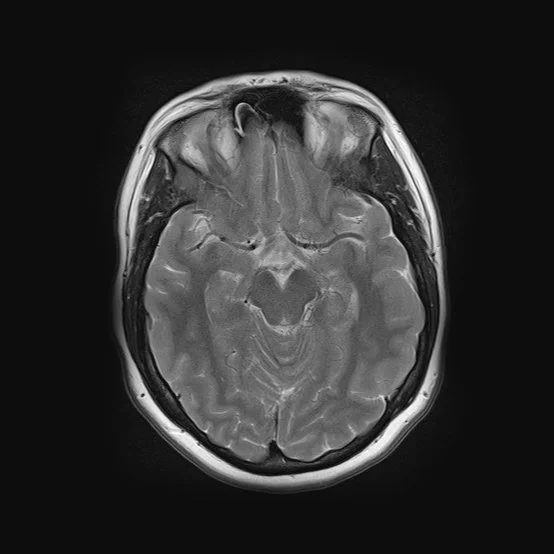

Taking an autoethnographic approach, the artist used her own MRI scans, arranging them to create a visual narrative that mirrors an evolutionary progression. This method not only highlights the physical shifts of the maternal body but also serves as a metaphor for the psychological and emotional changes that redefine the self.

By layering medical imagery into a conceptual framework, the work challenges the notion of identity as static, instead presenting it as fluid, evolving, and deeply intertwined with the lived experience of motherhood.